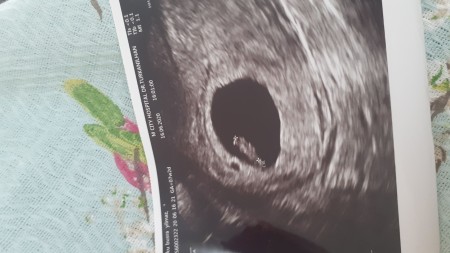

9 Haftalik 2 Aylik Gebelik Bebegin Kalp Atislari Goruluyor Crl Bas Popo Mesafesi 23 Milimetre Youtube